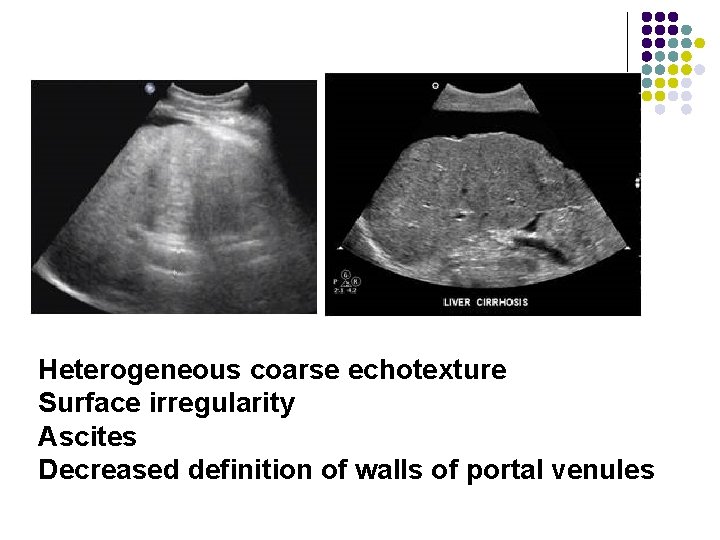

Hepatic Cirrhosis l l Surface irregularity Increased echogenicity Heterogeneous coarse echotexture Ascites

Heterogeneous coarse echotexture Surface irregularity Ascites Decreased definition of walls of portal venules

Heterogeneous coarse echotexture Surface irregularity Ascites Decreased definition of walls of portal venules